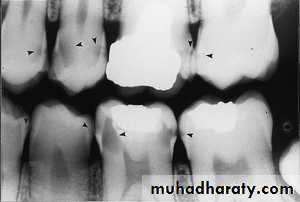

Teeth are composed of pulp (arrow on the secondmolar), enamel (arrow on the first molar), dentin (arrow onthe second premolar), and cementum (usually not visibleradiographically).